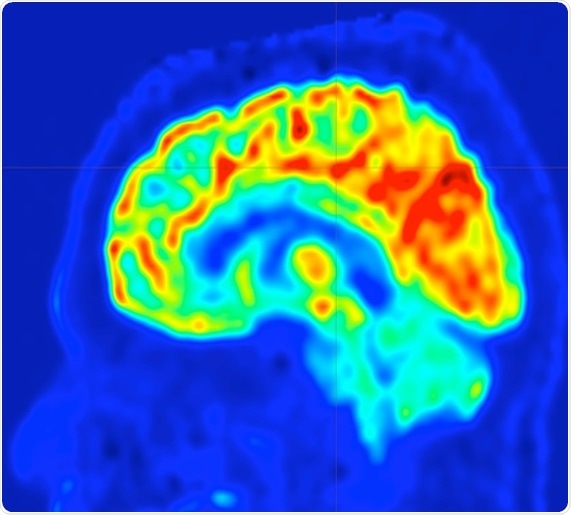

A brain map, created by a new approach developed at UVA, to guide surgery to prevent epilepsy seizures. Image Credit: University of Virginia Health System

This imaging approach is significant as it creates 4D brain maps which offer additional sensitivity over standard-of-care imaging by revealing rates of glucose uptake rather than final absolute glucose uptake. This imaging approach might be beneficial as it may offer non-invasive localization of potential epileptic foci.”

UVA’s new approach uses an enhanced form of positron-emission tomography (PET) to measure glucose use in the brain. This allows doctors to pinpoint the trouble spot in the brain that is triggering seizures. Once that spot is identified, it can be removed surgically, stopping the seizures.

PET scans have been used in the past to identify epilepsy trouble spots, but such scans have limited accuracy and often fail to identify an appropriate target. So a team of UVA researchers, backed by the UVA Brain Institute, developed the new approach, called “parametric dynamic FDG-PET imaging” (p-dFDG-PET).